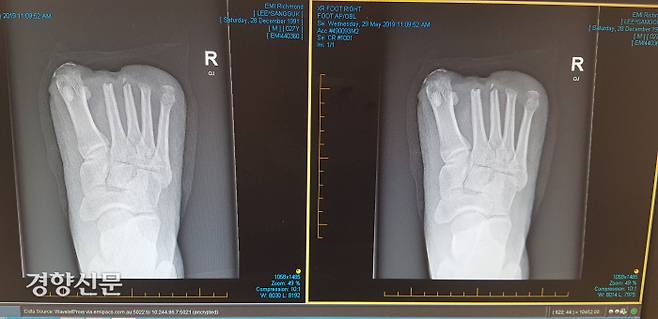

2019년 3월 12일, 8만t 규모의 대형선박에서 일하던 이상국씨(31)는 사고로 발가락 10개를 모두 잃었다. 당시 호주 멜버른 부두에 정박한 선박에서는 체인블록(거중기)을 이용한 엔진 부품 정비 작업이 한창이었다. 거중기 아래에는 기관장과 이씨를 비롯한 선원들이 있었다. 이씨는 취업한 지 한달도 되지 않은 3기관사였다.

거중기가 6t 무게의 엔진 부품을 끌어올릴 때였다. 거중기에 달린 체인이 끊어지면서 부품이 이씨의 발 위로 떨어졌다. 너무 순식간이라 피할 새도 없었다. 발가락 10개가 잘렸고 현장은 아수라장이 됐다. 필리핀 국적의 선원 두명이 들 것을 가져왔다. 이씨는 호주의 한 병원으로 후송됐다. 배가 정박한 상태에서 일어난 사고라 빠른 후송이 가능했다.

이씨는 자신의 사건을 두고 ‘나쁜 사례’라고 말했다. 혼자 싸워 여기까지 왔지만 그러지 않을 수 있도록 제도가 만들어져야 한다는 것이다. 그간 이씨는 절단과 피부이식 등 6차례의 대수술을 받았다. 사고와 그 이후의 스트레스로 수면제를 복용하지 않고는 잠을 자지 못하는 상황이다.